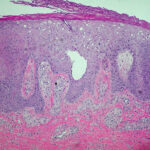

Histopathology . Pyoderma gangrenosum exhibits a dichotomous tissue reaction, showing central necrotizing suppurative inflammation, usually with ulceration, and a peripheral lymphocytic vascular reaction comprising perivascular and intramural lymphocytic infiltrates, usually without fibrin deposition or mural necrosis . Transitional areas show neutrophils in a loose cuff around the angiocentric lymphocytic infiltrates, defining a mixed lymphocytic and neutrophilic vascular reaction termed a Sweet’s-Iike vascular reaction . Bullous lesions may also demonstrate a Sweet’s-like vascular reaction with perivascular disintegrating neutrophilic infiltrates and hemorrhage without mural necrosis or luminal fibrin deposition. At variance with Sweet’s syndrome is destruction of the connective tissue framework with resultant tissue pathergy . Although a leukocytoclastic vasculitis may be observed in areas of maximal tissue pathology, pyoderma gangrenosum does not reflect a primary vasculitis . In some cases a necrotizing pustular follicular reaction may be the central nidus of the lesion, particularly in the vesicular pustular variant associated with ulcerative colitis or hepatobiliary disease. In the superficial granulomatous variant, florid pseudoepitheliomatous hyperplasia may be observed along with the intraepithelial and superficial dermal suppurative granulomatous inflammation with admixed plasma cells and eosinophils . Gases of pyoderma gangrenosum associated with Grohn’s disease may have areas of granulomatous inflammation . |